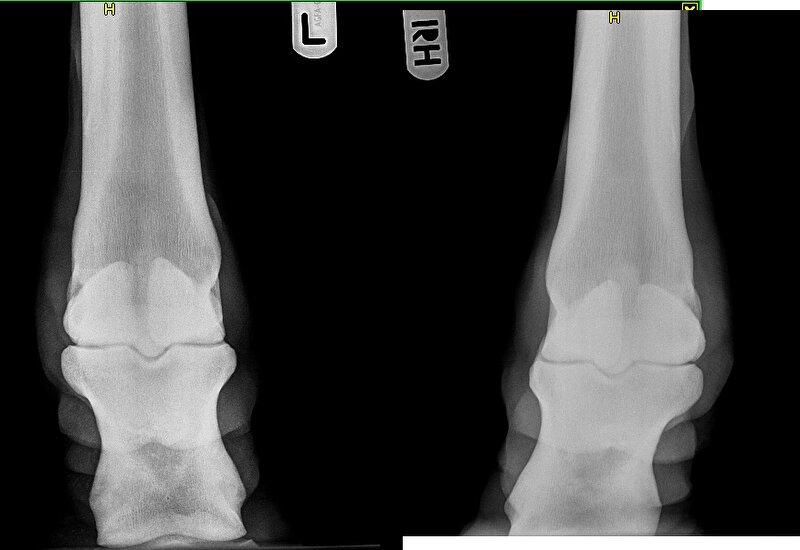

Vandaag de foto's opgehaald! :)

Kogelgewricht

Afbeelding

Spronggewricht

Nu woensdag maar afwachten.

Dierenarts vond haar in stap zuiver en in draf niet zozeer onregelmatig maar wat stijf. Ze zag de verdikking en gaf aan dat ze het logisch vond, dat ik dat uitgesloten wilde hebben. Allereerst foto's van het griffelbeentje. Prima in orde. Toen de pezen op de scan. Prima in orde. Het enige wat ze kon zien, was een verdikking van het weefsel, wat kan komen door een schop of ergens tegen aan stoten. Kortom blij dat, het uitgesloten is, alleen nog niets verder.